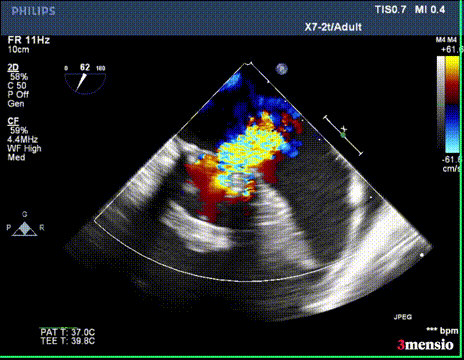

切割前彩超

第一次切割后,导丝紧,血流分为两束

第一次切割后,导丝松,血流又合为一束,但方向改变

第二次切割后,导丝紧,血流分为两束

第二次切割后,导丝松,血流已打散

切割时拉紧导丝两端,不切割时,放松导丝,解除对瓣叶的压力后,用彩超观察血流方向,切割成功后,可以观察到彩超血流的改变。

二尖瓣反流消失,跨瓣压差3mmHg;左室流出道血流速度正常